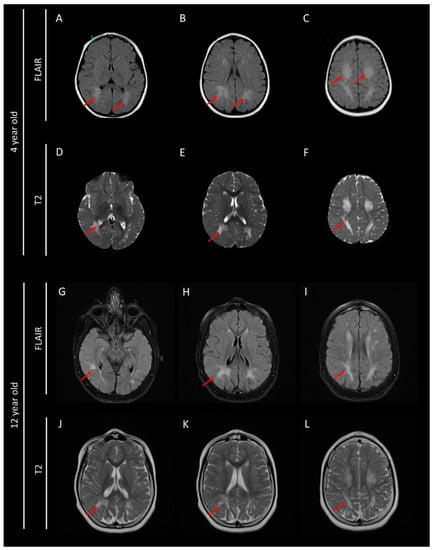

2. Case Presentation